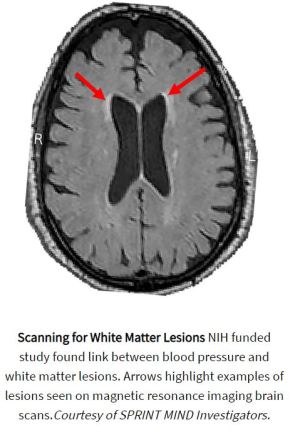

Brain Health Research: Controlling Blood Pressure Reduces Age-Related Cognitive Loss

In a nationwide study, researchers used magnetic resonance imaging (MRI) to scan the brains of hundreds of participants in the National Institutes of Health’s Systolic Blood Pressure Intervention Trial (SPRINT) and found that intensively controlling a person’s blood pressure was more effective at slowing the accumulation of white matter lesions than standard treatment of high blood pressure. The results complement a previous study published by the same research group which showed that intensive treatment significantly lowered the chances that participants developed mild cognitive impairment.

“These initial results support a growing body of evidence suggesting that controlling blood pressure may not only reduce the risk of stroke and heart disease but also of age-related cognitive loss,” said Walter J. Koroshetz, M.D., director of the NIH’s National Institute of Neurological Disorders and Stroke (NINDS). “I strongly urge people to know your blood pressure and discuss with your doctors how to optimize control. It may be a key to your future brain health.”